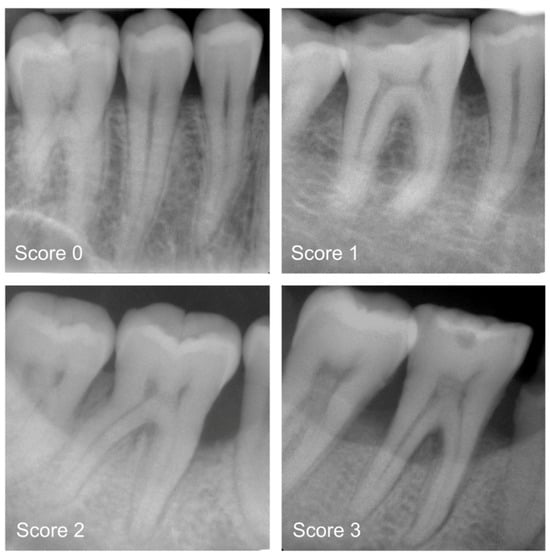

Only one study has incorporated transformer networks into periodontology. Specifically, Dujic et al. [49] evaluated Vision Transformer networks for automated periodontal bone loss (PBL) detection in periapical radiographs, comparing five models (ViT-base, ViT-large, BEiT-base, BEiT-large, and DeiT-base) which were utilized and evaluated based on accuracy (ACC), sensitivity (SE), specificity (SP), positive/negative predictive value (PPV/NPV), and area under the ROC curve (AUC). Using 21,819 anonymized radiographs labeled by dentists, the results showed high diagnostic accuracy (83.4–85.2%) and AUC scores (0.899–0.918). The model performed best on mandibular teeth (94.1–96.7% accuracy for anterior teeth) but had lower accuracy for maxillary posterior teeth (Figure 7). These Vision Transformers demonstrated promising diagnostic consistency, though further improvements are suggested, such as expanding datasets and incorporating precise region annotations for increased clinical applicability.

Figure 7. Periapical radiograph pictures for the following categories: mild radiographic periodontal bone loss (Score 1), moderate radiographic periodontal bone loss (Score 2), severe radiographic PBL extending to the mid-third of the root and beyond (Score 3), and healthy periodontium (Score 0). Reprinted from Ref. [49]. Copyright 2023, Diagnostics. This article is an open-access article distributed under the terms and conditions of the Creative Commons Attribution (CC BY 4.0) license.